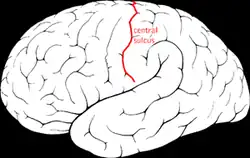

| Diagram showing the central sulcus of the brain. | |

Benign Rolandic epilepsy or self-limited epilepsy with centrotemporal spikes (formerly benign childhood epilepsy with centrotemporal spikes (BECTS)) is the most common epilepsy syndrome in childhood.[1][2] Most children will outgrow the syndrome (it starts around the age of 3–13 with a peak around 8–9 years and stops around age 14–18), hence the label benign.[3][4] The seizures, sometimes referred to as sylvian seizures, start around the central sulcus of the brain (also called the centrotemporal area, located around the Rolandic fissure, after Luigi Rolando).[5]